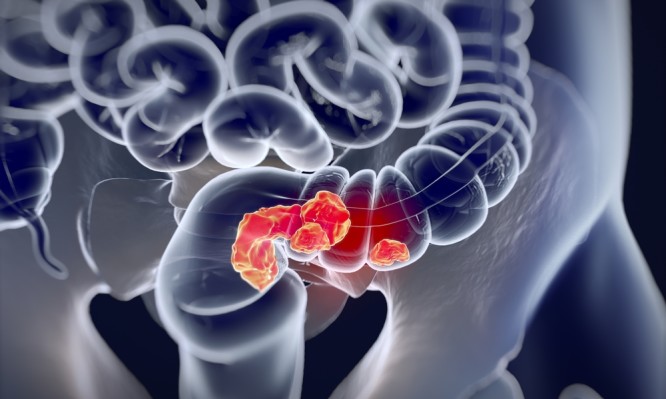

Καρκίνος του παχέος εντέρου: Αυξάνονται οι θάνατοι στους νέους και κανείς δεν ξέρει το γιατί – Ψάχνονται οι ειδικοί

Επίσης ανησυχητικό είναι ότι αυτή η αύξηση που παρουσιάζει ο καρκίνος του παχέος εντέρου σε ποσοστά εμφάνισης και σε θανάτους δεν φαίνεται να είναι το αποτέλεσμα κάποιας ευρύτερης ανίχνευσης καρκίνου του παχέος εντέρου στον γενικό πληθυσμό, αλλά εστιάζεται στους νεαρούς λευκούς Αμερικανούς.

Μια ανάλυση των στατιστικών από το 1970 έως το 2014 έδειξε ότι η τάση είναι πιο έντονη για τον επιθετικό καρκίνο που εξαπλώνεται από το παχύ έντερο σε άλλα όργανα του σώματος.

Καρκίνος του παχέος εντέρου: Λεπτομέρειες για τη νέα έρευνα

Για τις ανάγκες της έρευνας, οι επιστήμονες χρησιμοποίησαν στοιχεία από το Εθνικό Κέντρο Στατιστικής Υγείας. Επικεντρώθηκαν σε άτομα ηλικίας 20 έως 54 ετών από το 1970 έως το 2014 και συγκεκριμένα σε 242.000 θανάτους από καρκίνο του παχέος εντέρου σε αυτή την ηλικιακή ομάδα.